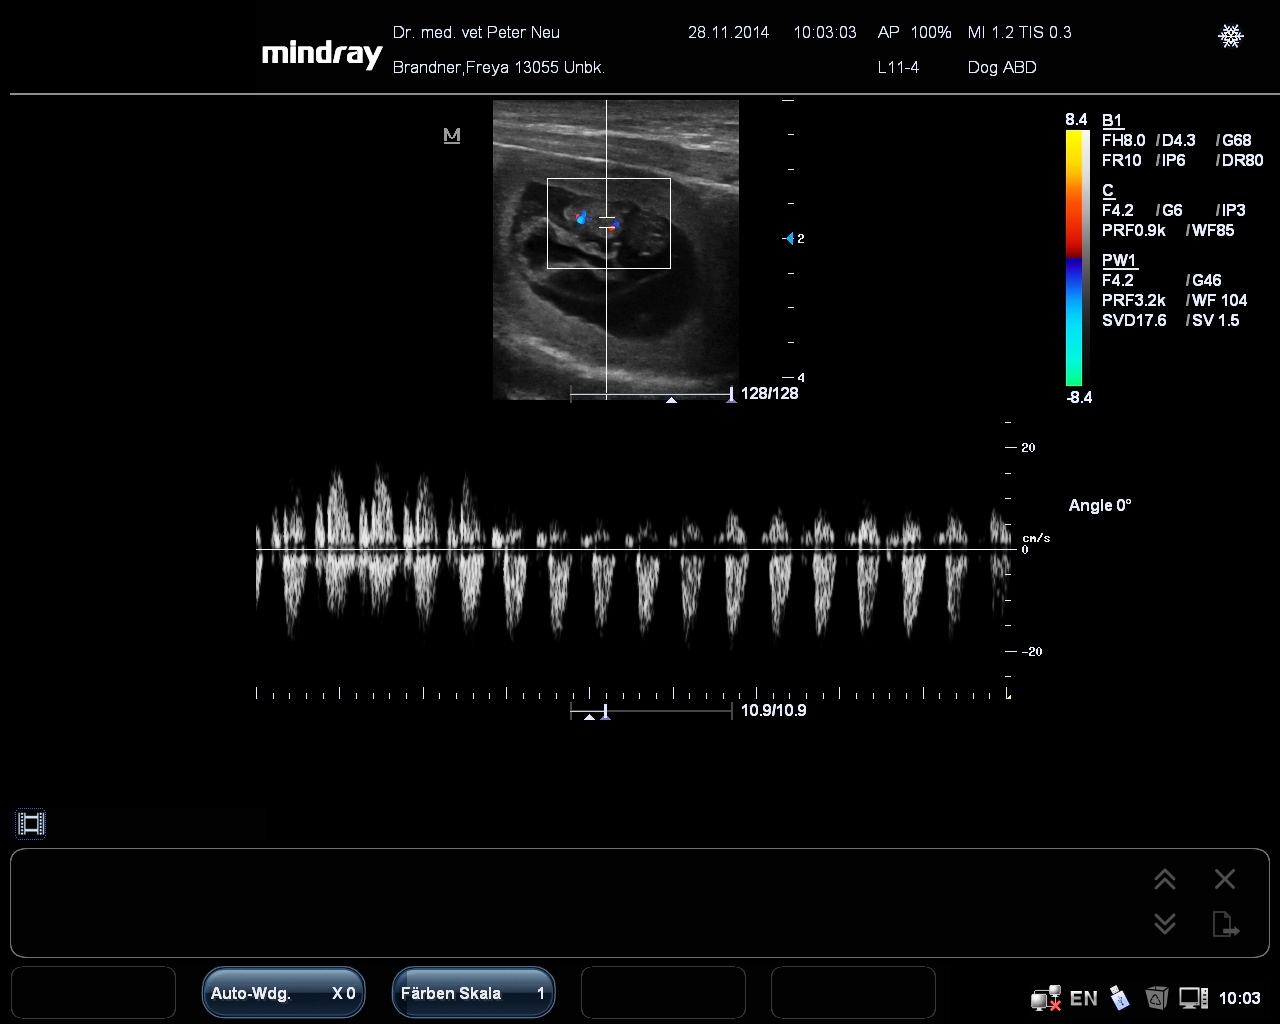

Das ist ein Bild mit dem neuen Gerät mit einem PW Doppler. Die Sonde liegt auf dem Herzen eines Hundewelpen.

Der Herzschlag des Welpen ist über Lautsprecher zu hören und auch grafisch dargestellt (die Zacken auf der unteren Linie). So kann man bei einer Geburt beurteilen, ob es dem Welpen in der Mutter gut geht.